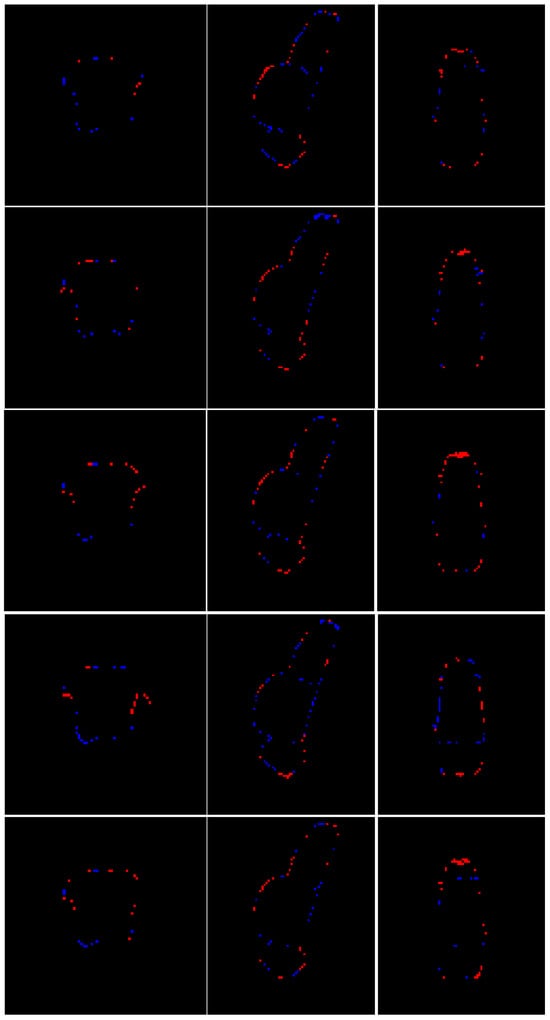

- Superior Segmentation Performance: The proposed modified U-Net architecture (with attention-enhanced skip connections and inception modules) significantly outperforms three comparative approaches in brainstem parcellation, achieving higher scores across all substructures (medulla, pons, and mesencephalon) and the whole brainstem.

- Technical Advancements: The success of attention mechanisms and inception modules highlights their value for complex anatomical segmentation, paving the way for similar adaptations in other small-structure parcellation tasks.

- Woo, S.; Park, J.; Lee, J.; Kweon, I.S. CBAM: Convolutional Block Attention Module. In Proceedings of the European Conference on Computer Vision (ECCV), Munich, Germany, 8–14 September 2018; pp. 3–19. [Google Scholar]